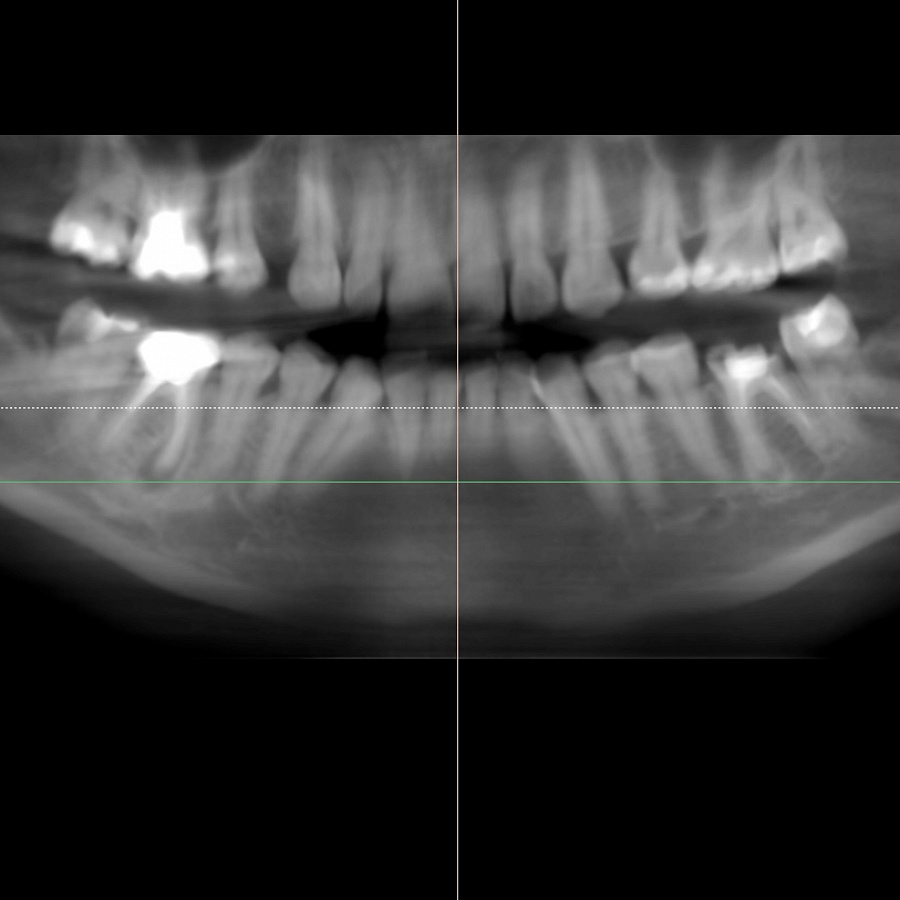

В ходе диагностики мы выяснили, что нижние шестерки вылечить невозможно. В таком случае необходимо удалить зубы и установить имплантаты.